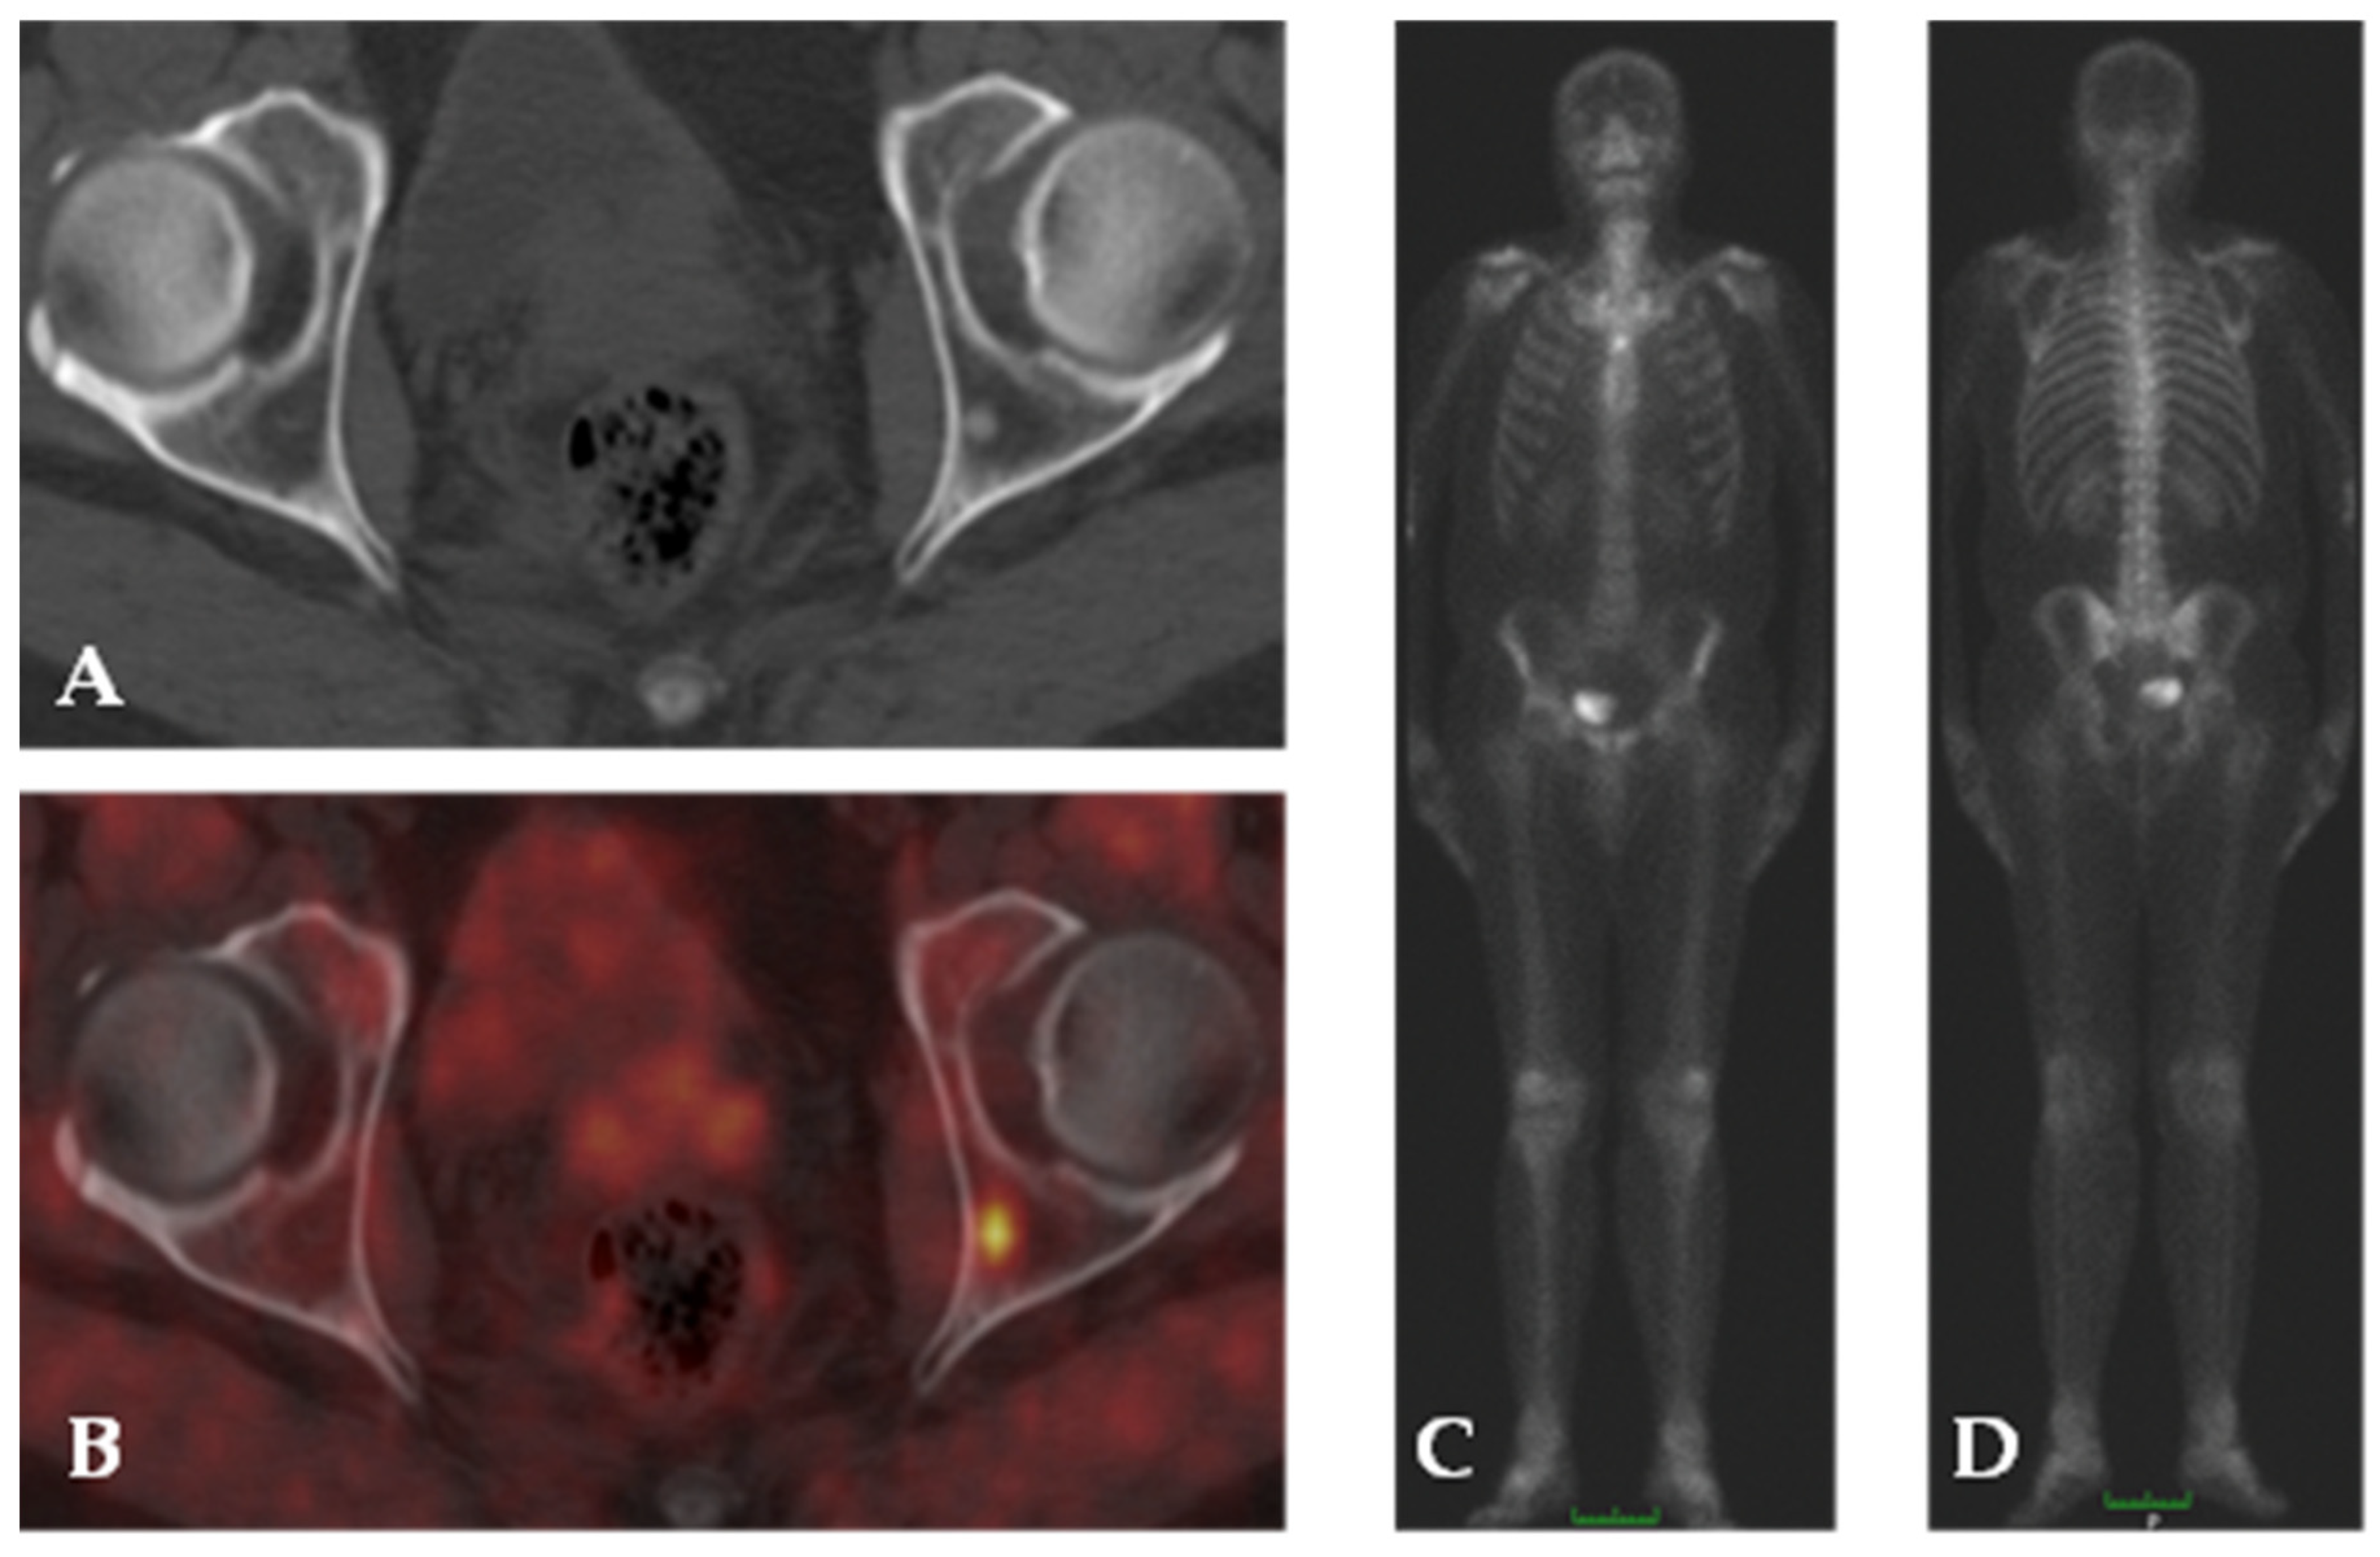

4.2. Choline

- Castellucci, P.; Ceci, F.; Fanti, S. Imaging of Prostate Cancer Using 11C-Choline PET/Computed Tomography. Urol. Clin. N. Am. 2018, 45, 481–487. [Google Scholar] [CrossRef]

- Pelosi, E.; Arena, V.; Skanjeti, A.; Pirro, V.; Douroukas, A.; Pupi, A.; Mancini, M. Role of Whole-Body 18F-Choline PET/CT in Disease Detection in Patients with Biochemical Relapse after Radical Treatment for Prostate Cancer. Radiol. Med. 2008, 113, 895–904. [Google Scholar] [CrossRef]

- Fuccio, C.; Castellucci, P.; Schiavina, R.; Santi, I.; Allegri, V.; Pettinato, V.; Boschi, S.; Martorana, G.; Al-Nahhas, A.; Rubello, D.; et al. Role of 11C-Choline PET/CT in the Restaging of Prostate Cancer Patients Showing a Single Lesion on Bone Scintigraphy. Ann. Nucl. Med. 2010, 24, 485–492. [Google Scholar] [CrossRef] [PubMed]